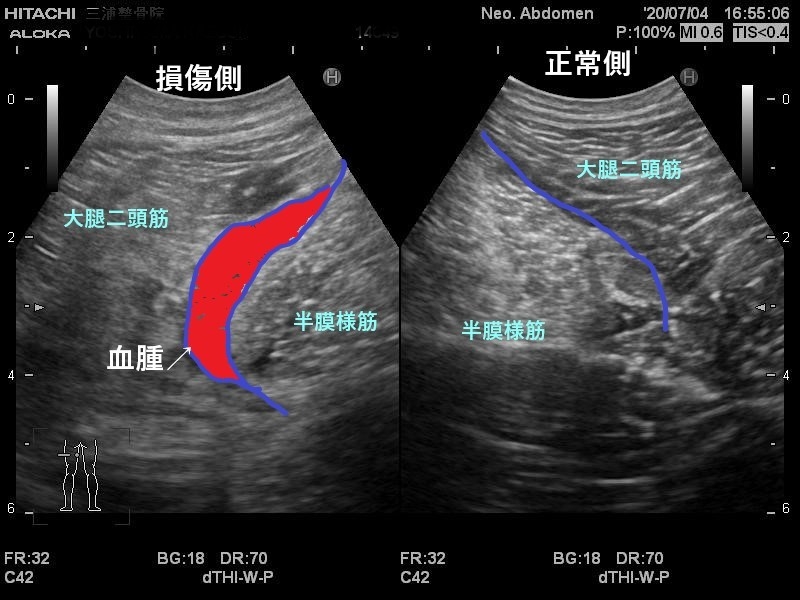

エコーではこのように写ります。

患側では大きく腫れて

正常な靭帯線維が見えないため

二分靭帯が断裂しています。

こういった画像で状態や動きも参考にしながら

最短で治していく方針を立てていきます。